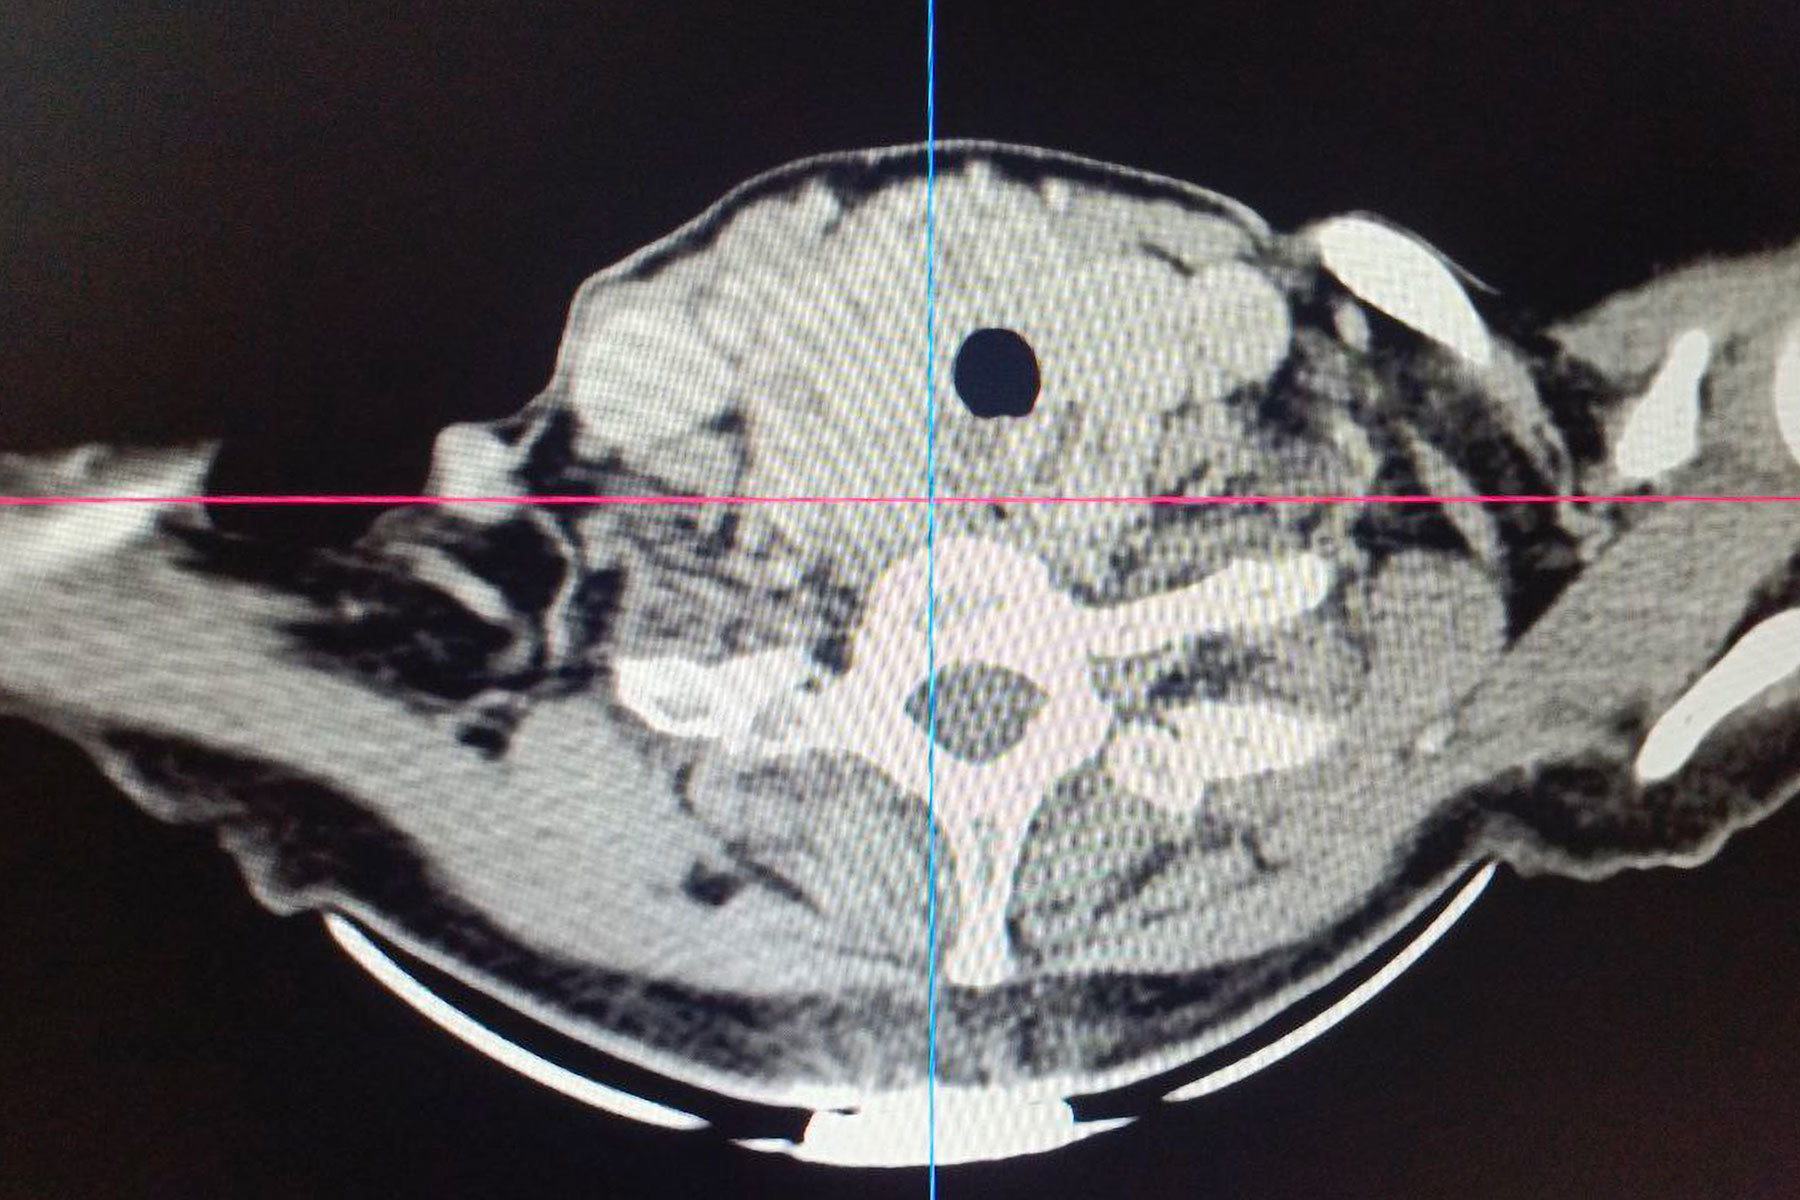

Операции предшествовало комплексное обследование, включавшее компьютерную и

Особую сложность представляло анатомическое расположение зоба. По словам хирурга, расположение зоба было частично загрудинным, образование опускалось за грудину примерно на две трети. А правая доля щитовидной железы подходила вплотную к плечеголовному стволу — крупному артериальному сосуду. Кроме того, зоб циркулярно охватывал трахею, сдавливая ее со всех сторон и вызывая у пациентки затруднение дыхания даже при небольшой физической нагрузке.